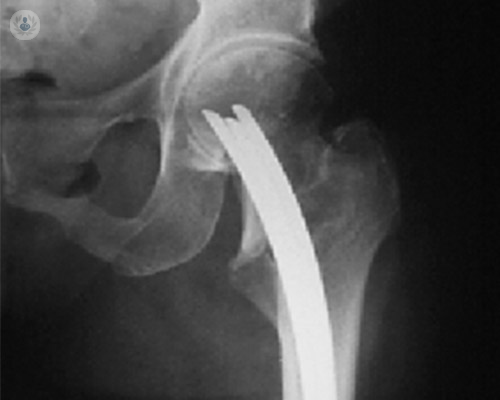

Reemplazo de cadera robótico de precisión submilimétrica: el nuevo estándar en recuperación y calidad de vida

La cirugía robótica permite una planificación personalizada y una ejecución con exactitud submilimétrica, mejorando la estabilidad, la seguridad y la recuperación funcional